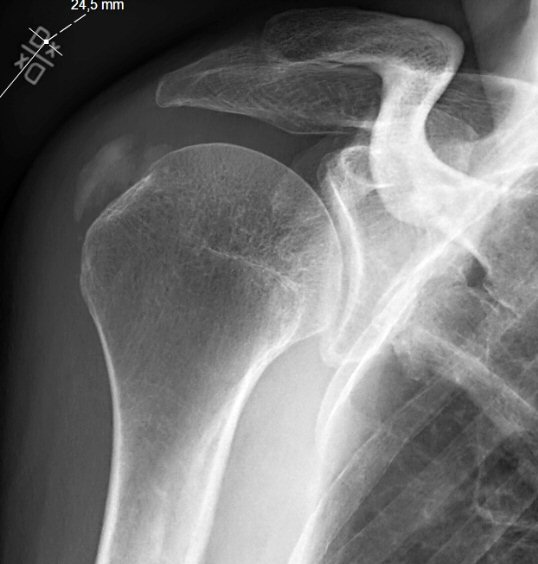

Två exempel på kalkaxlar, både med kraftig smärta och förhöjt CRP men återställda efter några dagar.

• Röntgenbild med typisk förkalkning i supraspinatussenan